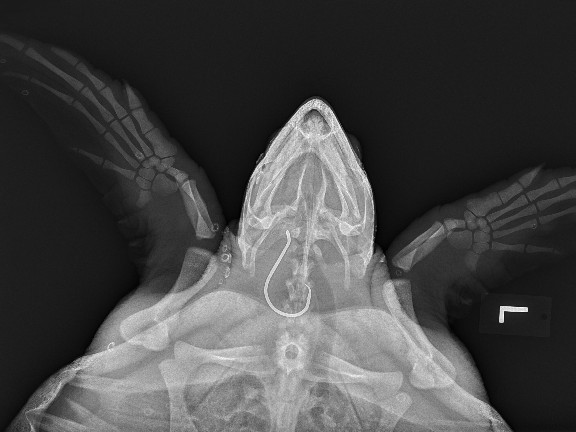

According to the Virginia Aquarium and Marine Science Center, 58 sea turtles have been hooked by anglers in the lower Chesapeake Bay and adjacent ocean waters by the end of June. The previous record for a year was 45 in 2018. All but one of this year’s turtles have been Kemp’s ridley turtles. The other was a loggerhead.

The Kemp’s ridley is the smallest and most endangered of the sea turtles. Adults are under 30 inches long and weigh between 70 and 100 pounds. Their shell is olive green, and can be almost round when looked at from above. Once a male enters the ocean after hatching, it never again puts a fin on land for the rest of its life. They nest in Mexico and Texas, not along the East Coast. The National Park Service reports that the greatest threat to the Kemp’s ridley is egg poaching, followed by entanglement in fishing gear, habitat degradation, and ocean pollution/marine debris. The common loggerhead turtle is hooked less often. They are usually over 30 inches long, and adults commonly weight 200 to 350 pounds. Loggerheads do nest in Virginia.